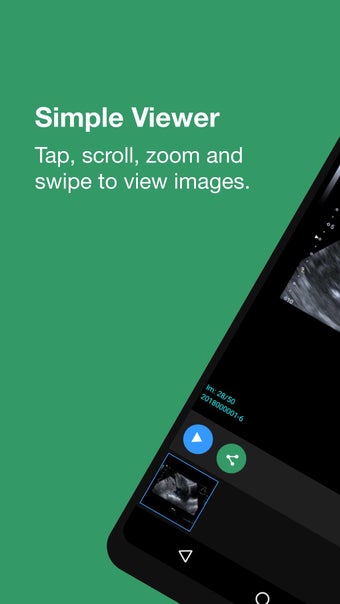

Este aplicativo é destinado a pacientes do PRP Diagnostic Imaging prática. O aplicativo myPRP permite que os pacientes visualizem seus exames, leiam os relatórios e marquem consultas.

O serviço é seguro, rápido e fácil de usar. Você não precisará esperar muito para que seus resultados estejam prontos para visualização. Você receberá uma mensagem SMS quando seus resultados estiverem prontos para visualização.